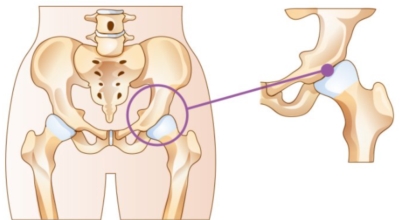

앞뒤로 움직이는 무릎 관절과는 다르게 고관절은 앞뒤 뿐만 아니라 좌우, 회전 등 자유롭게 움직임이 가능하며 운동 범위가 큰것이 특징입니다. 우리 몸 중 가장 큰 관절이기도 하다. 고관절에서 발생할 수 있는 고관절 통증 증상에 대해 알아보겠습니다.